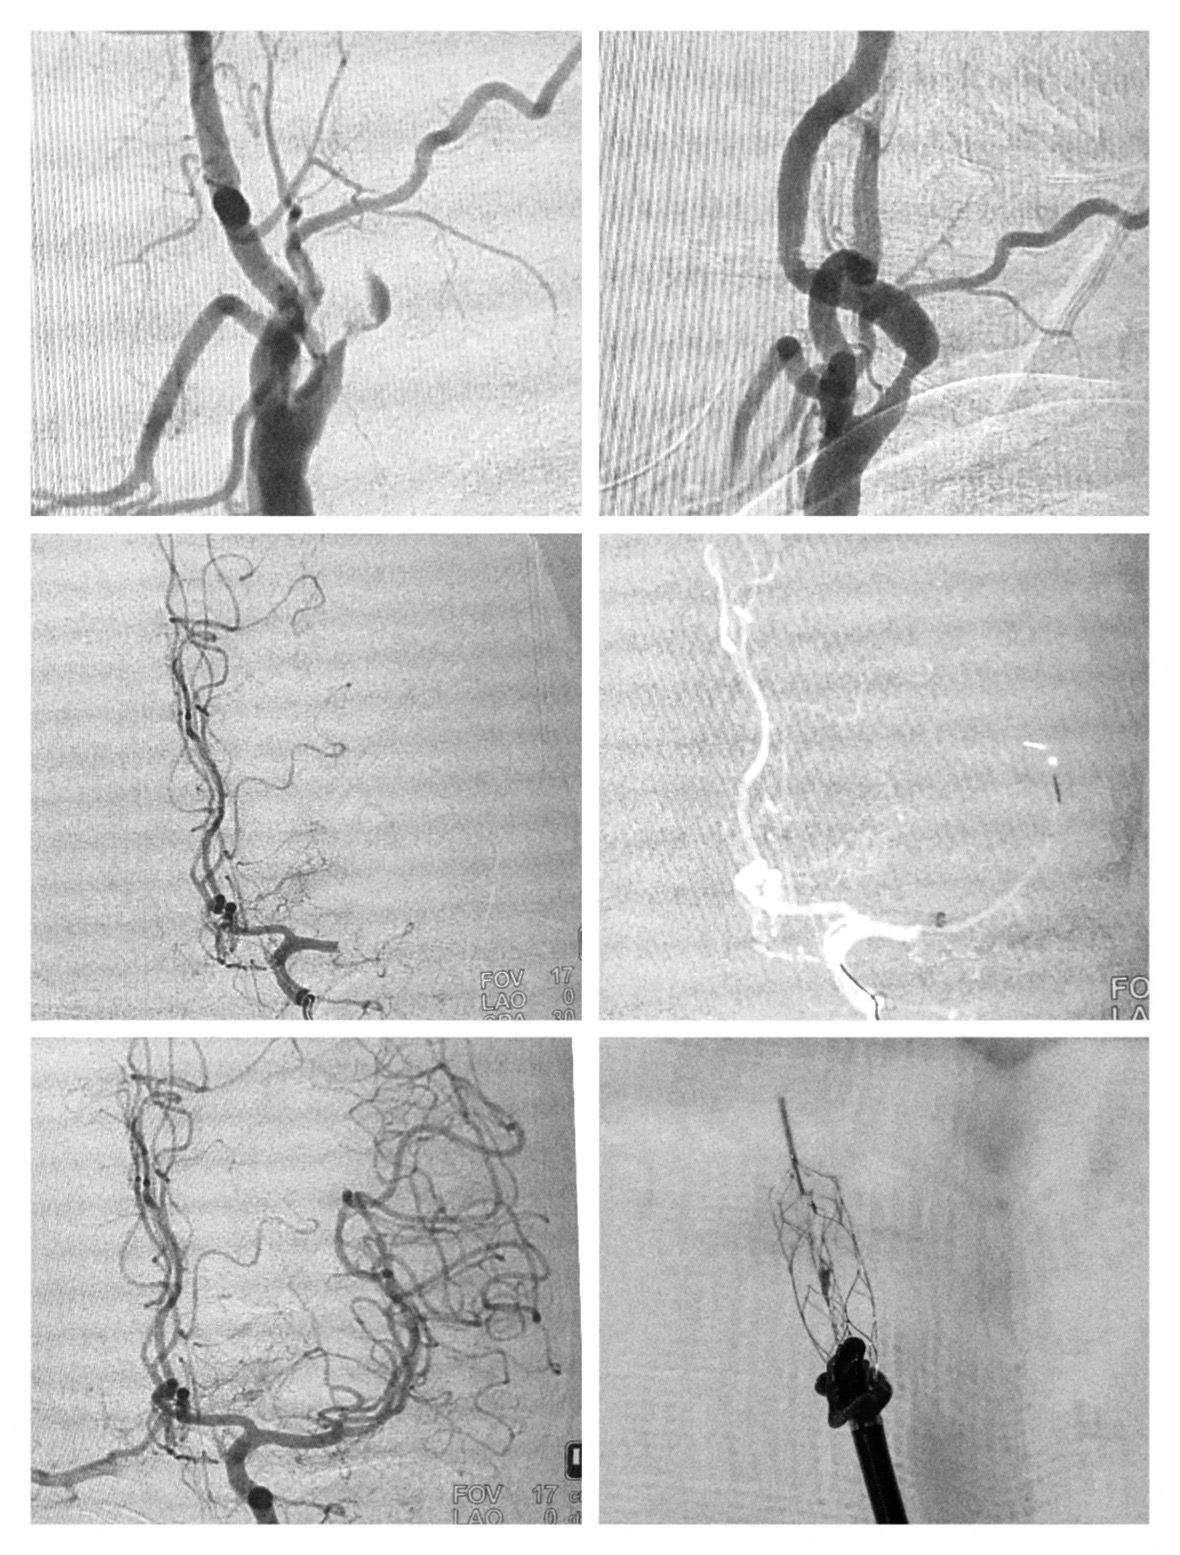

We managed three complex stroke cases, each involving tandem occlusions—the kind of vascular roadblocks that demand not only speed, but exceptional skill, coordination, and calm under pressure.

These cases aren’t easy. And three tandem occlusions in one week is no small feat.

They require advanced equipment, a deep understanding of cerebral vasculature, and a team that operates like a single, unified heartbeat.

And yet, case after case, we rose to the challenge—bringing blood flow back to the brain and giving each patient a fighting chance at recovery.

Here we are, proving once again that when seconds matter, we are more than ready – with Dr Samppathkumar Palanisamy at Royal Care Super Speciality Hospital, Coimbatore”